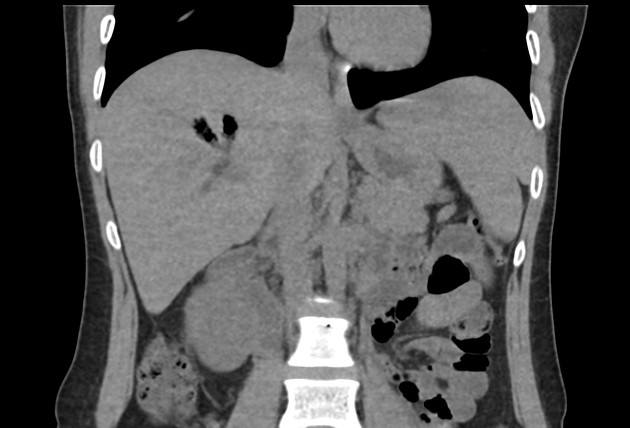

Khí đường mật

Khí đường mật - Ảnh 2

» Thông tin: Nữ giới – 30 tuổi.

» Lâm sàng: Đau mạn sườn phải / Tiền sử cắt túi mật.